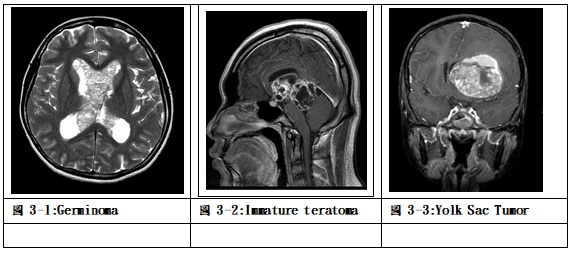

兒童顱內生殖細胞瘤相較於歐美國家約2.5%,在亞洲國家有較高的發生率,如日本、韓國及台灣的統計約達11-15%,在國內男女比率約3.4/1,平均診斷年齡為10.7歲。病理分類將生殖細胞瘤分為胚芽瘤(germinoma)、畸胎瘤(teratoma)、成熟畸胎瘤(mature teratoma)、不成熟畸胎瘤(immature teratoma)、畸胎瘤合併惡性轉型(teratoma with malignant transformation)、卵黃囊瘤(yolk sac tumor)、胚胎癌(embryonal carcinoma)及絨毛膜癌(choriocarcinoma),診斷上也可能是胚芽瘤含有合胞體滋養層巨細胞(germinoma with syncytiotrophoblastic giant cell; germinoma with STGC)或混合性生殖細胞瘤(mixed germ cell tumor)。好發的位置常見在松果體、蝶鞍上及基底腦核,有時診斷時已經散播到腦室及脊髓腔內。臨床表現依據不同部位有所不同,松果體區會壓迫大腦導水管導致水腦症,也可能壓迫或侵犯中腦背側四疊體,使眼球無法向上凝視及對焦,造成所謂落日眼(sunset eye; Parinaud’s syndrome)。位於蝶鞍上最常表現尿崩症、生長遲緩或視神經症狀;位於基底腦核的症狀為手腳緊繃無力或麻木。

除了胚芽瘤及成熟畸胎瘤外,其他種類的生殖細胞瘤可以在血清或腦脊髓液中檢測出α胎兒蛋白(α-fetoprotein)或β絨毛膜性腺激素(β-HCG)上昇,這兩種腫瘤指標可以作為生殖細胞瘤臨床診斷、治療成效與腫瘤復發的主要指標。

生殖細胞瘤的治療依據不同的病理分類有所不同。對於生殖細胞瘤中的胚芽瘤,從影像學上有典型的特徵且腫瘤指標沒有上升,可以考慮切片或不切片,加上包含腦室的放射線治療,可以得到有效的長期療效。然而影像學上的特徵若是診斷屬於畸胎瘤,建議先以手術切除腫瘤,若病理分類為成熟畸胎瘤,則不需要放射線或化學藥物治療,若病理診斷包含不成熟畸胎瘤或惡性轉型成份,則必須再加上放射線治療及化學藥物輔助。對於已知腫瘤指標其中一種上升的腫瘤,代表其中包含有惡性的腫瘤組織成份,如不成熟畸胎瘤、卵黃囊瘤、胚胎癌或絨毛膜癌等,治療必須合併手術切除、放射線治療及化學藥物輔助,才能達有效控制。